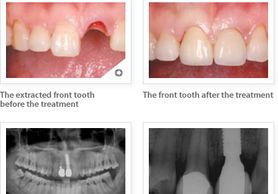

A dental implant is a metal device designed to replace missing teeth. The device is usually made out of titanium and is surgically placed into the jawbone where the tooth is missing. Unlike a dental bridge, an implant is permanent. A dental implant is designed to act as the tooth root and can anchor an artificial tooth or teeth such as a crown, bridge, or denture.